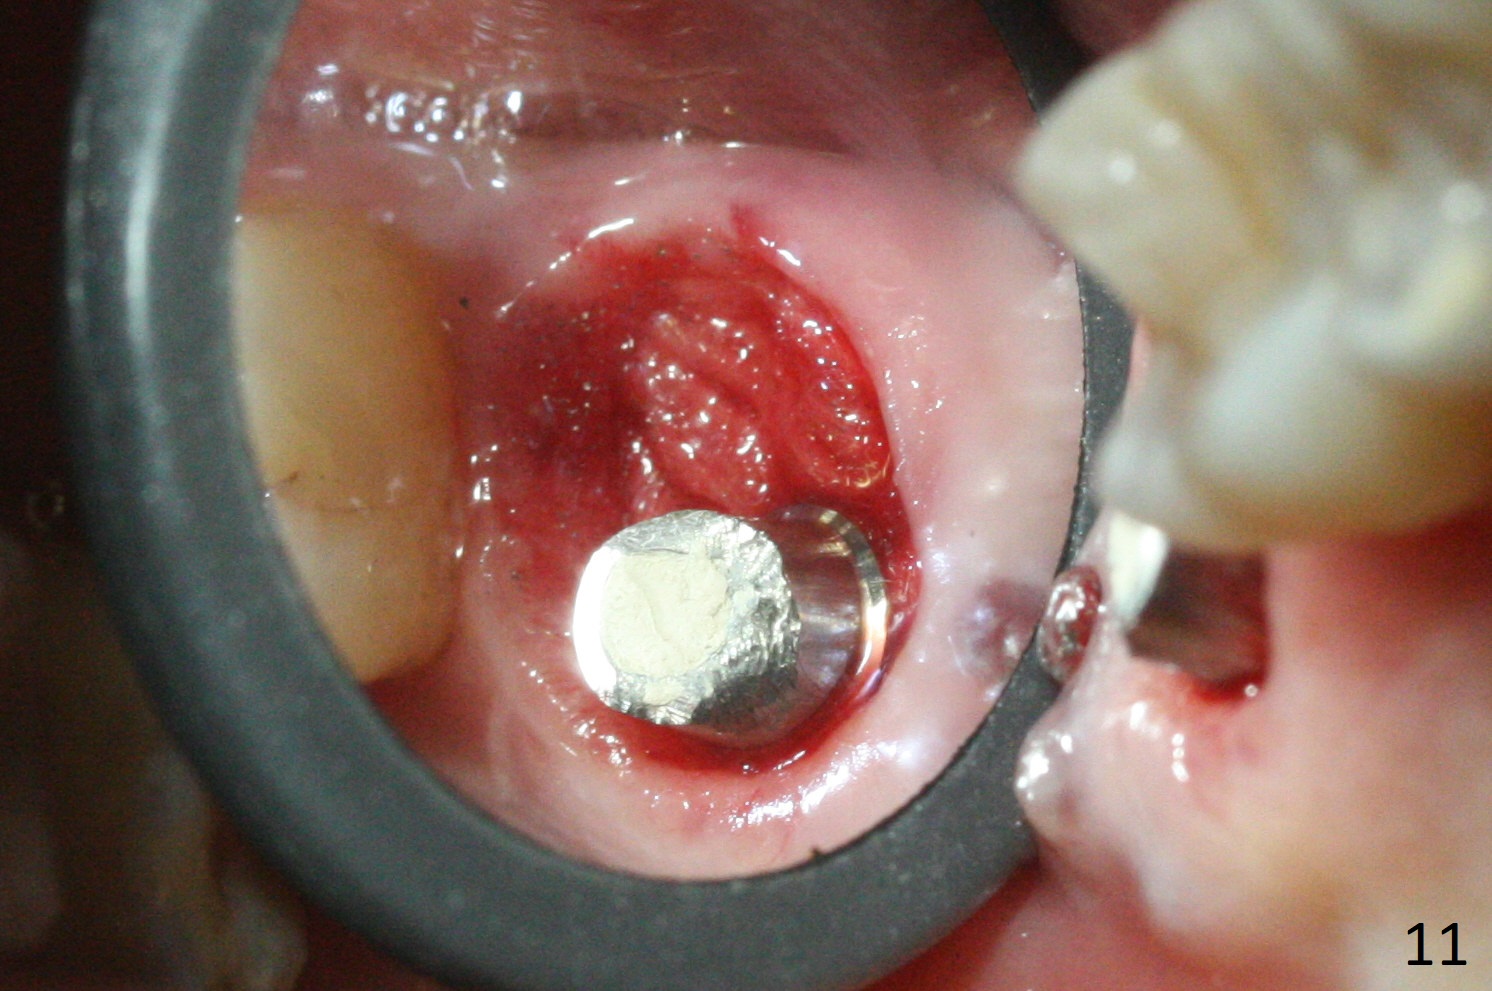

There is a fistula distal to the tooth #2 with deep pocket distopalatally (Fig.1 *), corresponding to palatal root fracture (Fig.2). There is a septum (Fig.3 S) between the buccal (B) and palatal (P) sockets. Osteotomy is initiated in the center of the septum (Fig.4 black circle). In fact the center of the socket is buccal (red circle), in which osteotomy should have been established because of the presence of the distopalatal bony defect associated with the root fracture and the distal fistula. The less ideal initial osteotomy leads to palatal placement of the implant and abutment (Fig.11 vs. 12).

Fig.5 shows the mesial slope of the socket (M), which is more or less the center of the socket mesiodistally. If the osteotomy were set up in the red circle (Fig.6) in the mesial slope (Fig.8 green dashed line), the trajectory of 4.5x11 mm dummy implant (Fig.7) would be more ideal (Fig.8 red outline) with more native bone contact. Finally a longer IBS implant is placed (4.5x15 mm, Fig.9,10) to achieve primary stability (50 Ncm). When the provisional is removed for impression 3 months 10 days postop, the implant is found to have been placed distopalatally (Fig.13), which should have been avoided. It appears essential to use guide for a distal implant. It is agonizing to re-encounter the off-axial implant (Fig.14) and the distopalatal access hole (Fig.15) 1 year post cementation. It is also amazing that the abutment screw has not loosened. A fair-sized piece of bone graft has just been removed buccally (Fig.15,16). The patient complains of sensitivity 2 years 3 months post cementation, although there is no abnormality around the implant crown. Guided surgery is essential to avoid restoration complication. There is no thread exposure nearly 3 years post cementation; in fact the apical portion of the abutment is covered by the bone (Fig.17,18).